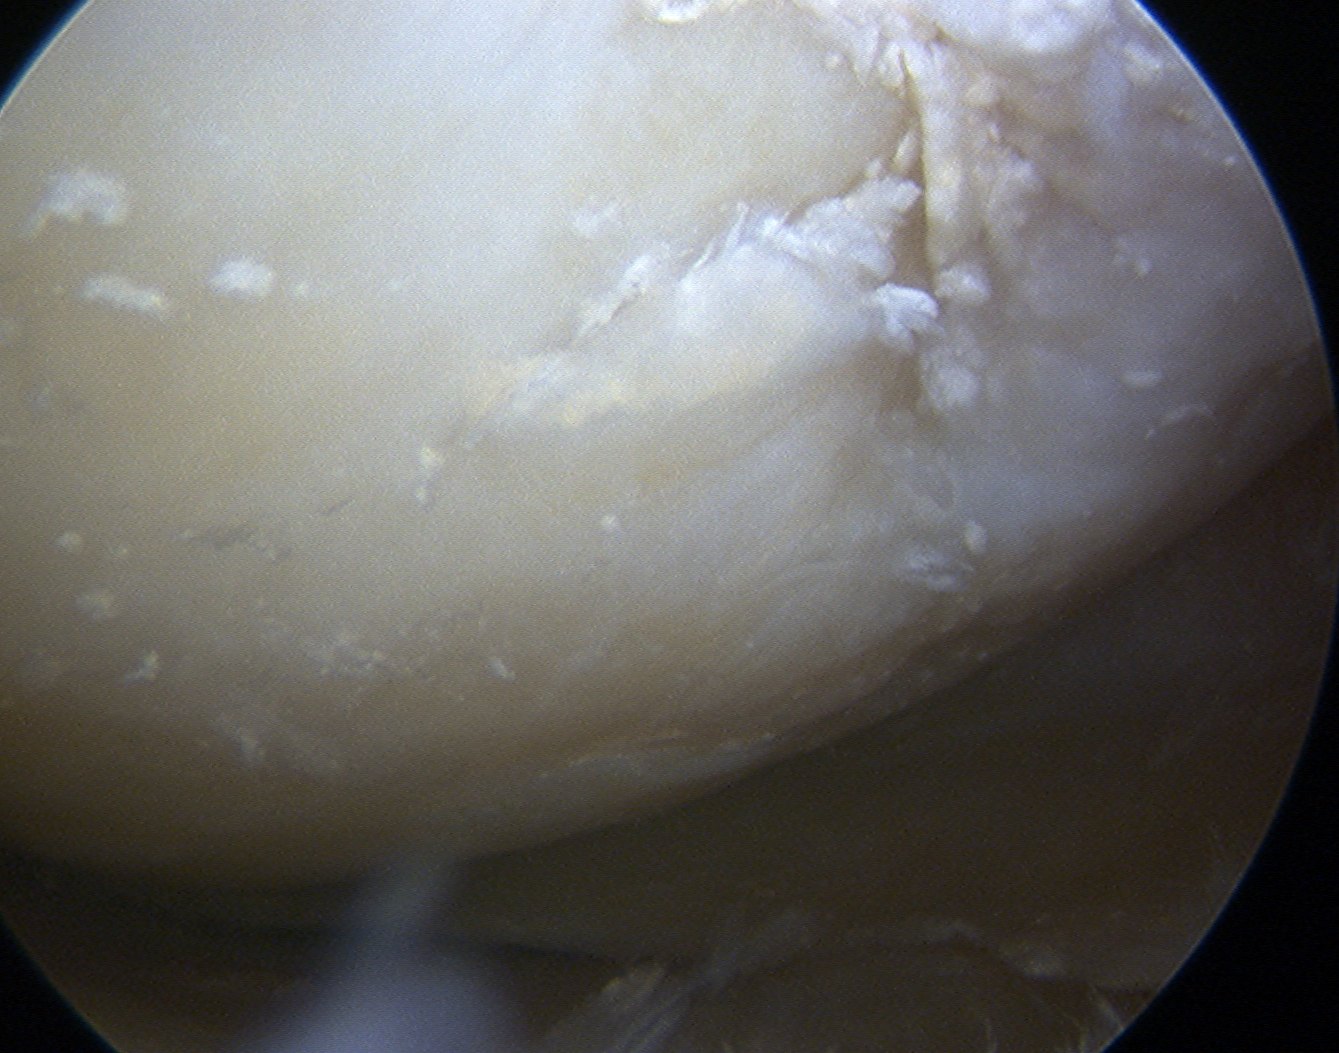

CPPD deposited in

- joint capsule

- articular cartilage

- fibrocartilage / meniscus

Crystals seen at margin of degenerating cartilage

- pyrophosphate generated at chondrocyte surface in abnormal cartilage

- combine with calcium to form crystals